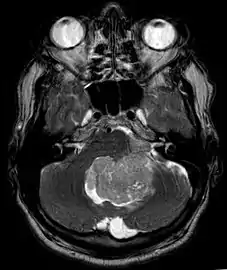

Ependymoma of 4.ventricle in MRI.